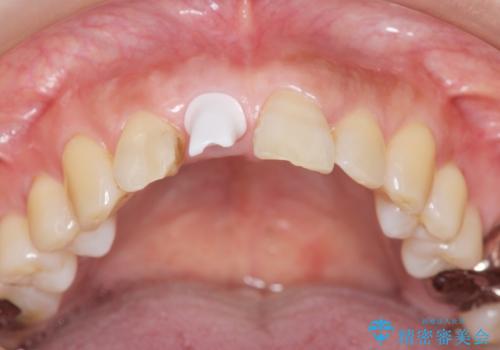

骨造成を伴う前歯のインプラント治療

- 前歯を外傷により失い、審美性の改善を求めて来院されました。

横の歯を削る必要のあるブリッジ治療、着脱の必要な入れ歯に強い抵抗があったためインプラント治療を計画します。

審美的・機能的に良好な位置に埋入するには、骨量が十分ではなかったため骨の造成を併用したインプラント埋入外科手術を行います。

前歯のインプラントを審美的に仕上げるには、インプラント周囲に十分な骨の量と厚みのある歯肉、そして埋入位置の精密な位置付けが重要です。